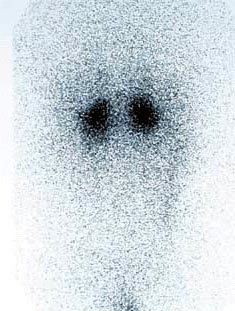

CaseYW01

- Age/Sex: 50M

- Chief Complaint: 頭痛,発汗過多,動悸,体重減少

- Clinical

Course: アルコール性肝炎にて経過観察中。最近1年間、高血圧症の診断で降圧薬を内服している。

- Lab. Data: 末梢血中濃度 Epinephrine 43 pg/ml (基準値 0-80),

Norepinephrine 31400 pg/ml (基準値 90-420), Dopamine 122 pg/ml

(基準値 0-30)

- Images:

- X-CT

- 131I MIBG,

48h

123I

MIBG, 24h

123I

MIBG, 24h

あなたの診断は What

is your first impression?

123I

MIBG, 24h

123I

MIBG, 24h